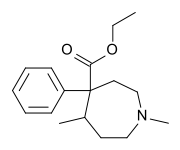

The first fully synthetic opioid was meperidine (later demerol), found serendipitously by German chemist Otto Eisleb (or Eislib) at IG Farben in 1932.[228] Meperidine was the first opiate to have a structure unrelated to morphine, but with opiate-like properties.[199] Its analgesic effects were discovered by Otto Schaumann in 1939.[228] Gustav Ehrhart and Max Bockmühl, also at IG Farben, built on the work of Eisleb and Schaumann. They developed "Hoechst 10820" (later methadone) around 1937.[230] In 1959 the Belgian physician Paul Janssen developed fentanyl, a synthetic drug with 30 to 50 times the potency of heroin.[211][231] Nearly 150 synthetic opioids are now known.[228]

Phenylpiperidines

- Pethidine (meperidine)